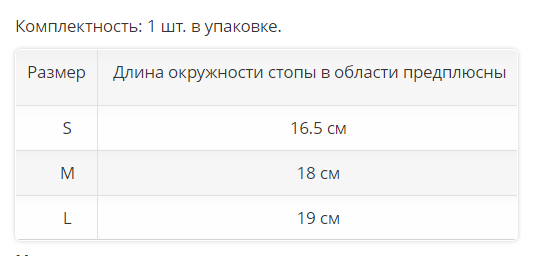

Комплектность: 1 шт. в упаковке.

| Размер |

Длина окружности стопы в области предплюсны |

| S | 16.5 см |

| M | 18 см |

| L |

19 см |